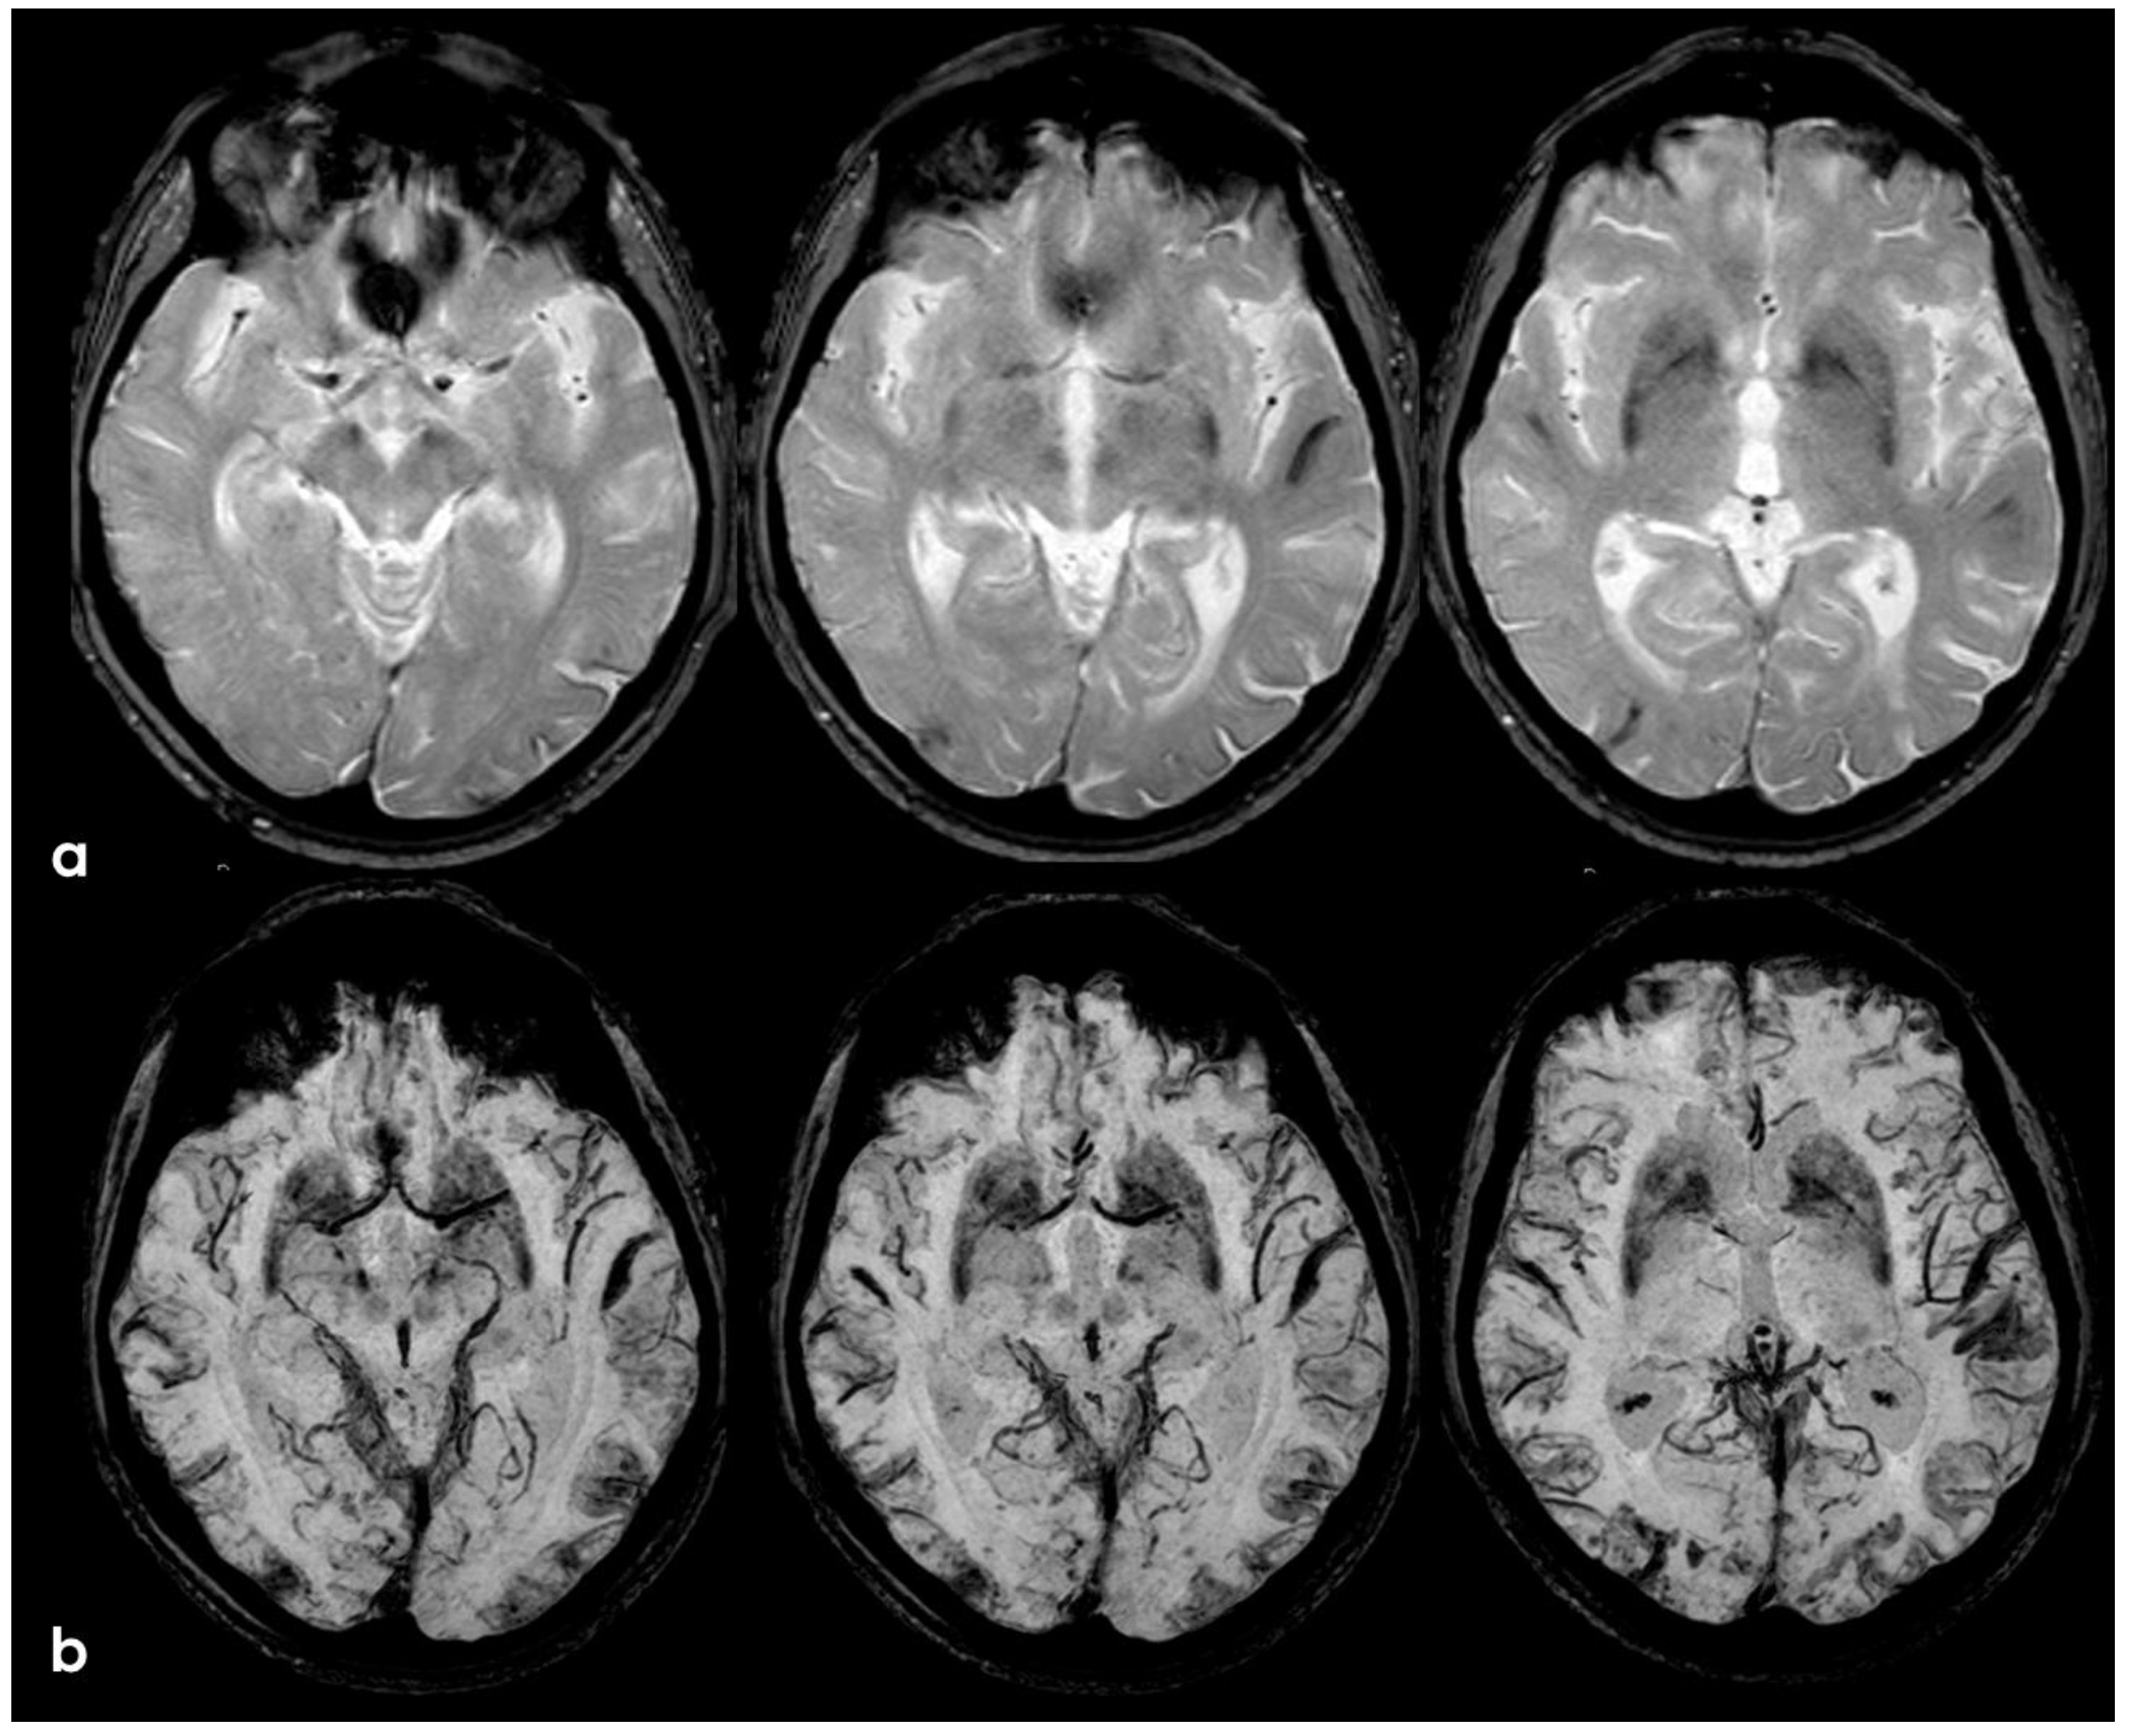

3. May 2014: CAA-Related Inflammation

5. February 2017: First Recurrent CAA-Related Inflammation

7. April 2018: Second Recurrent CAA-Related Inflammation

8. April 2018: Third Recurrent CAA-Related Inflammation